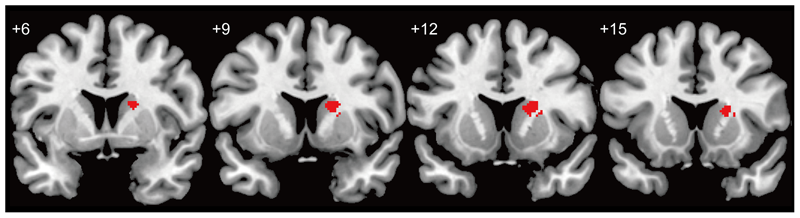

Voxel-based morphometry results showed that the gray matter density of the right dorsal striatum [top peak = (26, 14, 12)] of the in-relationship group was significantly lower than that of the no-relationship group (Table 1; Figures 1 and 2). Furthermore, because we did not find any significant correlation between average beta-value in significant clusters and SHS scores [two groups (68 participants): r(66) = -0.120, p = 0.331; in-relationship group (36 participants): r(34) = -0.114, p = 0.508], the significant difference in gray matter density in the right dorsal striatum could be primarily attributed to being in a romantic relationship. In the whole-brain analysis, we did not find any significant group differences except in the right dorsal striatum [top peak = (26, 14, 12); FWE-corrected p = 0.029; number of voxels = 2].

FIGURE 2

Cluster location related to being in a romantic love. Red area indicates differences in gray matter density between groups (no-relationship > in-relationship). The threshold for a difference in gray matter density was set at a voxel level of p < 0.05 (t > 2.765), FWE-corrected with an anatomical striatal mask.